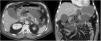

La pancreatitis aguda es una patología común y potencialmente grave que tiene un curso clínico muy variable. Este artículo pretende revisar el papel de las distintas técnicas de imagen en el manejo de esta entidad, describir sus principales manifestaciones radiológicas y la nomenclatura específica asociada a esta entidad.

Acute pancreatitis is common; the clinical course of this potentially severe condition varies widely. This paper aims to review the role of different imaging techniques in the management of acute pancreatitis, describe the main imaging findings for this entity, and explain the terms and criteria used to classify them.